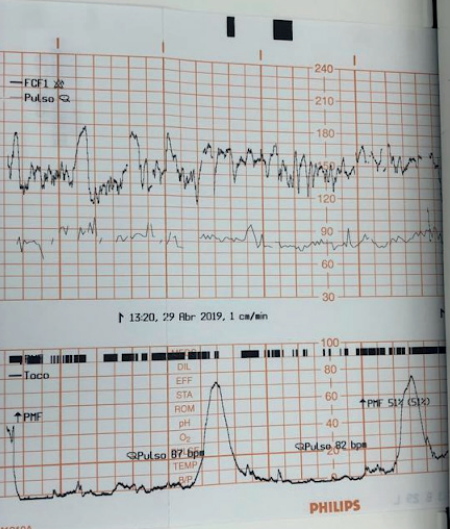

A principal ferramenta para o diagnóstico do sofrimento agudo é a cardiotocografia (CTG). A sua interpretação baseia-se na análise de múltiplos parâmetros:

- Linha de Base: Frequência cardíaca fetal (FCF) média em um traçado de 10 minutos. O normal situa-se entre 110 e 160 batimentos por minuto (bpm). Valores acima de 160 bpm definem taquicardia, e abaixo de 110 bpm, bradicardia.

- Variabilidade: Oscilações da FCF em torno da linha de base. A variabilidade moderada (6 a 25 bpm) é considerada normal e um forte indicador de um sistema nervoso autônomo íntegro. A variabilidade ausente é um sinal alarmante.

- Acelerações Transitórias: Aumentos temporários da FCF, considerados o melhor marcador de bem-estar fetal. Para fetos com idade gestacional (IG) > 32 semanas, define-se como um aumento de 15 bpm por 15 segundos.

- Desacelerações: Quedas transitórias da FCF, classificadas em:

- Tipo I (Precoce ou DIP I): Queda gradual e simétrica da FCF, cujo ponto mais baixo (nadir) coincide com o pico da contração uterina. É causada pela compressão do polo cefálico (reflexo vagal) e não se associa à hipóxia.

- Tipo II (Tardia ou DIP II): Queda gradual com nadir posterior ao pico da contração. Este padrão indica insuficiência uteroplacentária e hipóxia fetal.

- Tipo III (Variável ou Umbilical): Queda abrupta e de morfologia variável, causada pela compressão do cordão umbilical. Podem não estar associadas a sofrimento fetal, mas critérios como duração superior a 60 segundos, queda abaixo de 70 bpm e retorno lento à linha de base indicam mau prognóstico.

- Padrão Sinusoidal: Um padrão ondulatório, rítmico e regular, que é um sinal ominoso de anemia fetal grave e hipoxemia, com alto risco de óbito intraútero.

Os traçados da CTG intraparto são classificados em três categorias:

- Categoria 1: Traçado normal, com FCF basal entre 110-160 bpm, variabilidade moderada e ausência de desacelerações tardias ou variáveis preocupantes. A conduta é o seguimento do trabalho de parto.

- Categoria 3: Traçado anormal. Inclui padrão sinusoidal ou ausência de variabilidade associada a desacelerações tardias/variáveis recorrentes ou bradicardia. A conduta é a realização imediata de medidas de ressuscitação intrauterina e parto pela via mais rápida.

- Categoria 2: Traçado indeterminado, que não se enquadra nas categorias 1 ou 3. Exige medidas de ressuscitação intrauterina. Se o padrão não melhorar em até 30 minutos, indica-se a resolução da gestação.